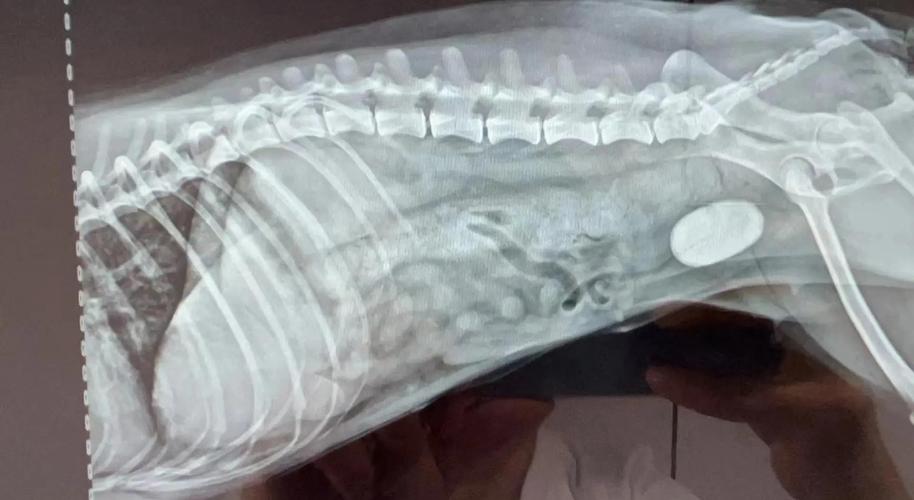

〖Four〗、膀胱破裂后,犬只会表现出一系列症状。首先,尿液进入腹腔,导致腹部逐渐增大,尿量明显减少或完全无尿排出。在导尿过程中,尿量明显减少,且尿液中可见血液。当尿路阻塞导致膀胱破裂时,原先的排尿困难症状会突然消失。通过腹部触诊,可以感知到腹壁的紧张感,而膀胱膨胀的抵抗感则消失,腹腔内出现液体波动。